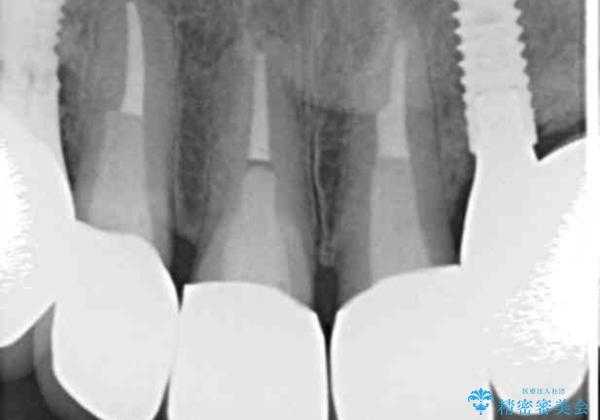

[ 精密セラミック治療 ] 前歯の破折 根尖病変

- 左上前歯のぐらつき、痛みを感じ来院されました。

検査の結果、痛みのあった歯は割れており抜歯が必要な状態、残りの前歯も根尖に病変が認められ根管治療が必要な状態です。

割れてしまった歯だけではなく、全体的な治療を希望されたので丁寧に既存のクラウン・メタルコア・虫歯を除去し治療を行っていきました。

割れてしまっていた歯は、抜去を行いインプラントを用いた機能の回復を行っています。

きっちりと根管治療を行ったことで、X線写真からも根尖病変の改善傾向が認められます。